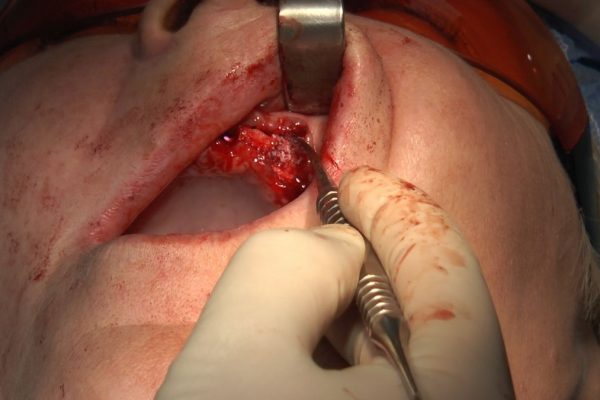

W ostatni weekend czerwca 2018 roku kursanci II Sezonu Preludium Implantologii odbyli piątą, finałową sesję, która w całości podporządkowana była praktyce. W ciągu dwóch dni zabiegowych Lekarze uczestniczący w szkoleniu przeprowadzili szereg zabiegów pod kierunkiem dr n.med. Violetty Szycik. Wszczepili 17 implantów oraz przeprowadzili ekstrakcje i zabiegi regeneracyjne kości. Zabiegi były wykonywane także w sedacji dożylnej z udziałem specjalisty anestezjologii i intensywnej terapii dr Jolanty Grzybowskiej. Preludium implantologii to nowy program edukacyjny dla adeptów implantologii stomatologicznej, którego celem jest wprowadzenie do implantologii poprzez pozyskanie wiedzy w szerokim zakresie i uwzględnieniem szczegółów mających decydujące znaczenie dla powodzenia leczenia implantologicznego. Ale tak jak wszystkie szkolenia w Instytucie Vivadental, w tym wiodące Practiculum Implantologii, zorientowane jest na praktyce i samodzielnym wykonywaniu zabiegów pod kierunkiem Mentora. To najlepsza edukacja w medycynie zabiegowej, a zarazem najlepszy start do implantologii.